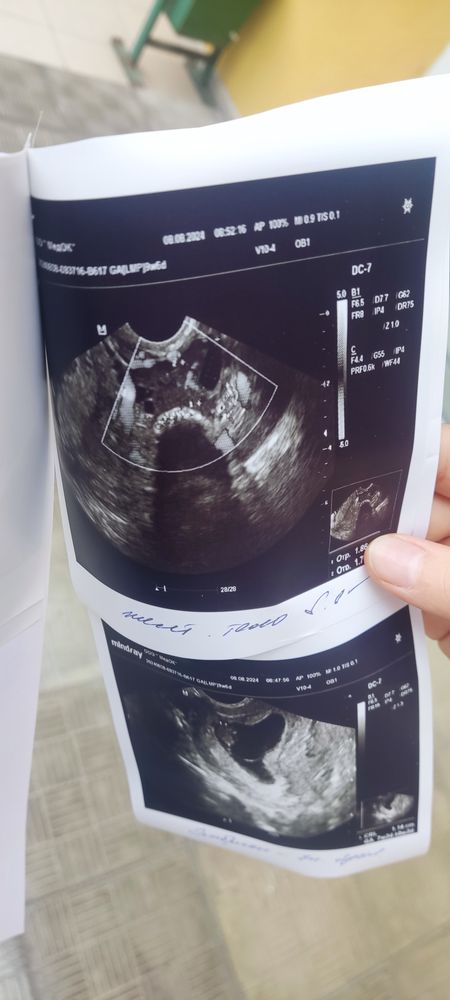

Подскажите про УЗИ

Все норм в узи, тонус отдыхать больше ❤️

Нормальное УЗИ ,тонус бывает у многих на таком сроке.Побольше отдыхайте и не поднимайте тяжести.

Вообще у вас тонус, я бы к врачу сходила, тонус на маленьком сроке опасен